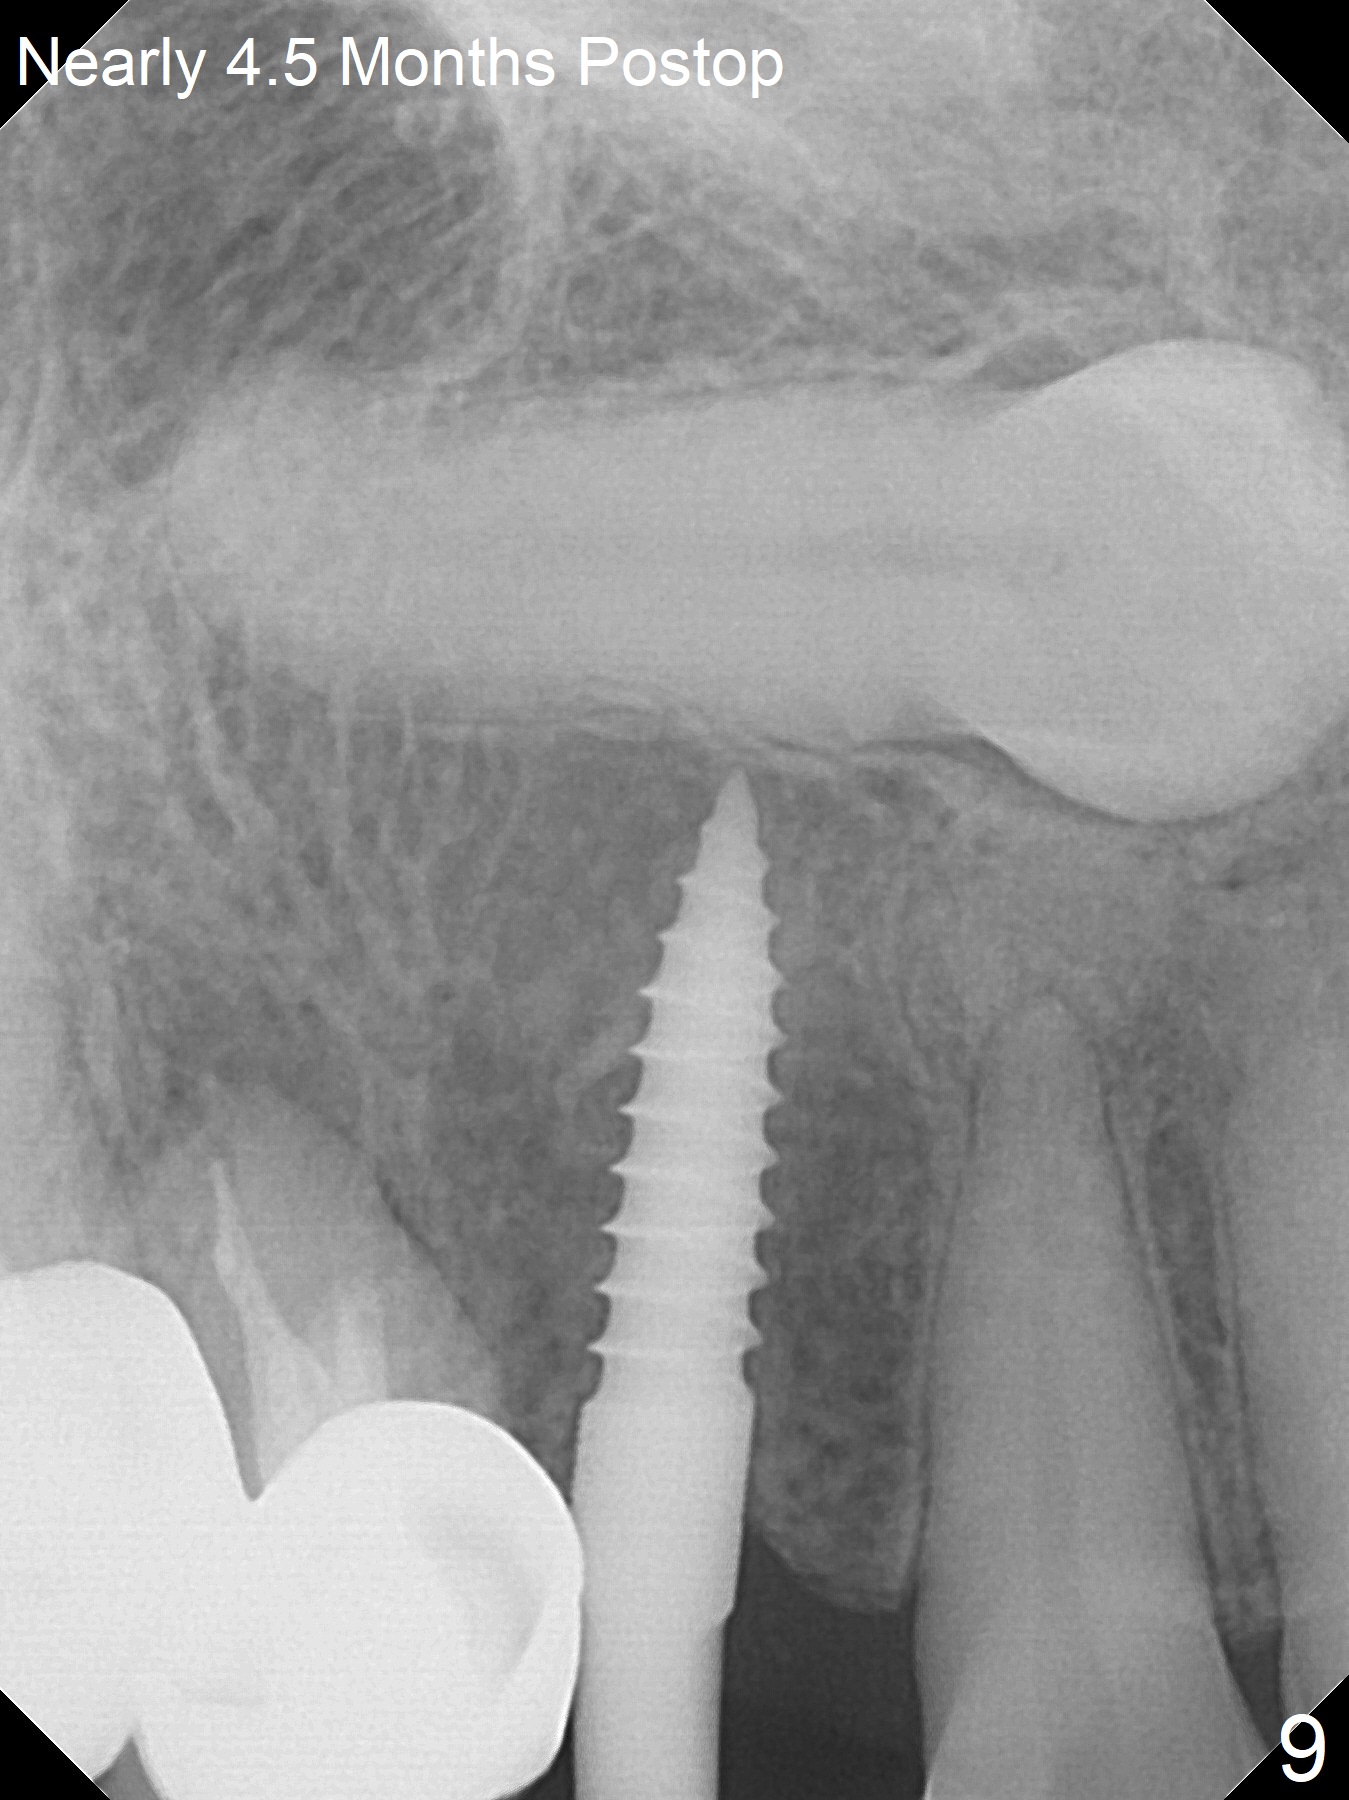

After removal the pontic of a cantilever FPD (Fig.1), a residual root is found at #6 with the buccal concavity (Fig.2 *). The ridge is narrow with flap elevation (Fig.3). PA taken with a 1.2 mm drill for 14 mm shows a horizontally impacted canine (Fig.4: #6). When the osteotomy is finished without apparently buccal perforation (Fig.5), the trajectory is buccal. When a 3x14 mm (12.5 mm in bone) 15 degree angled 1-piece implant is placed with normal trajectory (Fig.6), the buccal plate is perforated. As the implant is redirected so that the apical end of the implant does not stick out buccally, the trajectory returns buccal (Fig.7). The buccal aspect of the abutment is heavily reduced for an immediate provisional. The perforation is repaired with Vanilla Graft and Collagen Dressing before suturing. CT should have been taken preoperatively; the osteotomy should have been initiated as palatal as possible, as compared to that in Fig.5. When the 1st drill is used. it should be checked for restoration. An angled abutment does not help the trajectory substantially. The implant is loose 1.5 months (partially due to mastication); after retightening, CT is taken (Fig.8). The implant is within the bone. If the implant becomes loose again, extract the impacted canine and place the longest implant (22 mm) palatally. The implant is stable nearly 4.5 months postop (Fig.9). The patient is not satisfied with buccally-placed crown. The implant is removed with bone graft 6 months postop.